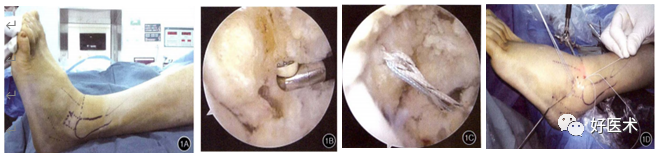

上图为关节镜下改良Broström术式治疗慢性踝关节外侧副韧带损伤。a.患者术前绘制体表标志;b.在腓骨远端置入锚钉;c.两颗锚钉各带一根线;d.使用肝针或suturelasso进行过线(来自参考文献1)